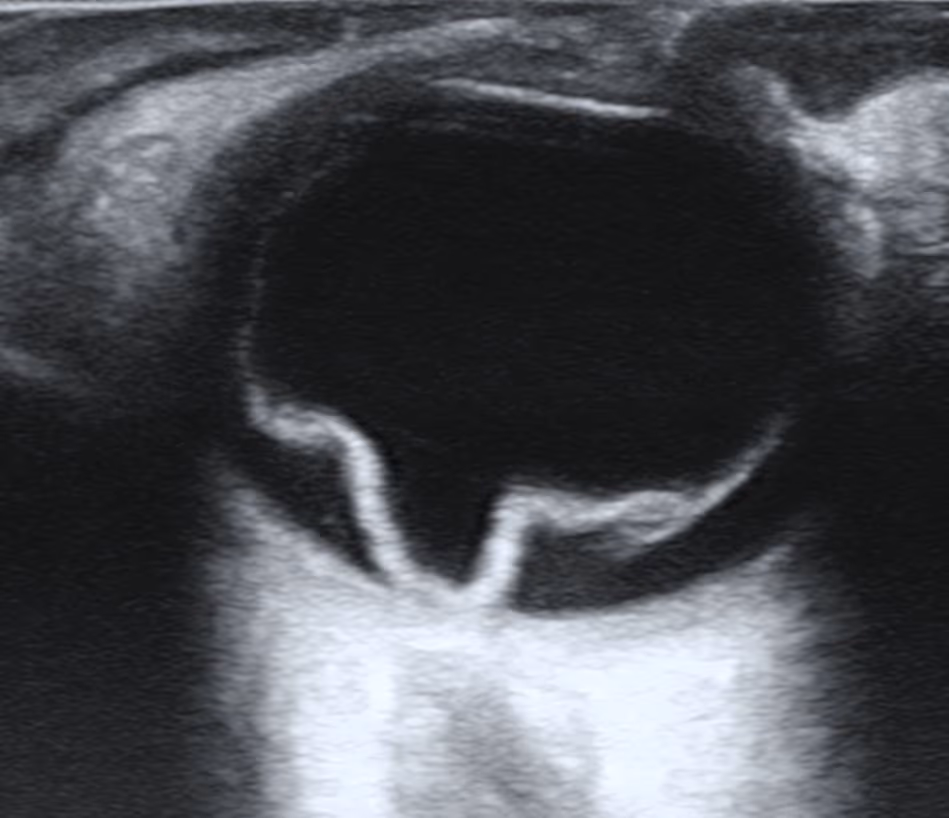

Quando o meio ocular está opaco (catarata avançada, hemorragia vítrea) e impede a visualização direta, podem ser usados: ultrassonografia B-scan (muito útil — mostra a retina descolada como uma membrana flutuante), fotografia de fundo de ampla angulação e OCT para avaliar envolvimento macular.